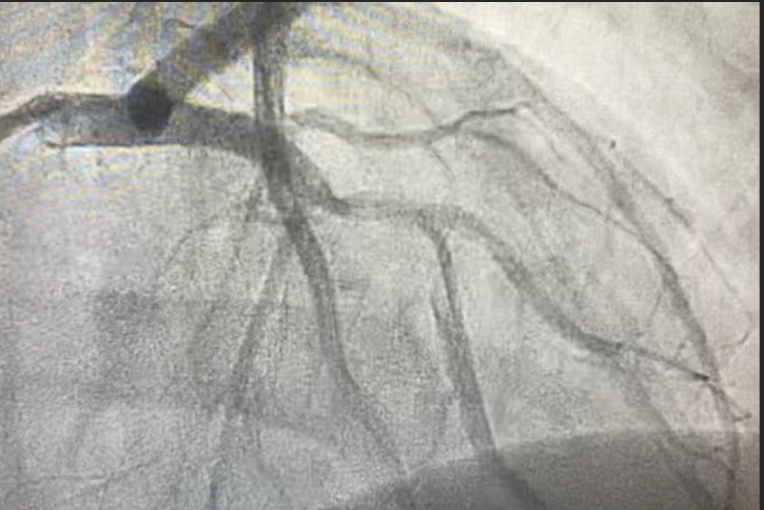

Cardiac Catheterization Findings

- Dissection of the left anterior descending (LAD) artery extending beyond the takeoff of the principal diagonal branch;

- Total occlusion of the apical LAD, likely due to distal embolization;

- Two drug-eluting stents were successfully deployed to restore flow.

SCAD angiographically presents with hallmark features including intramural hematoma, with or without an intimal tear, and typically involves the LAD artery.1,3 In our case, the LAD dissection was confirmed and treated with PCI. While conservative management is generally favored due to the high spontaneous healing rates, PCI is indicated in high-risk cases with ongoing ischemia or hemodynamic instability, as in our patient.1,2,3